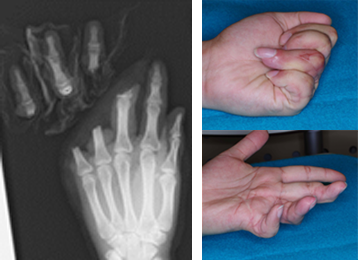

左写真:左中・環・小指完全切断

右写真:術後2年